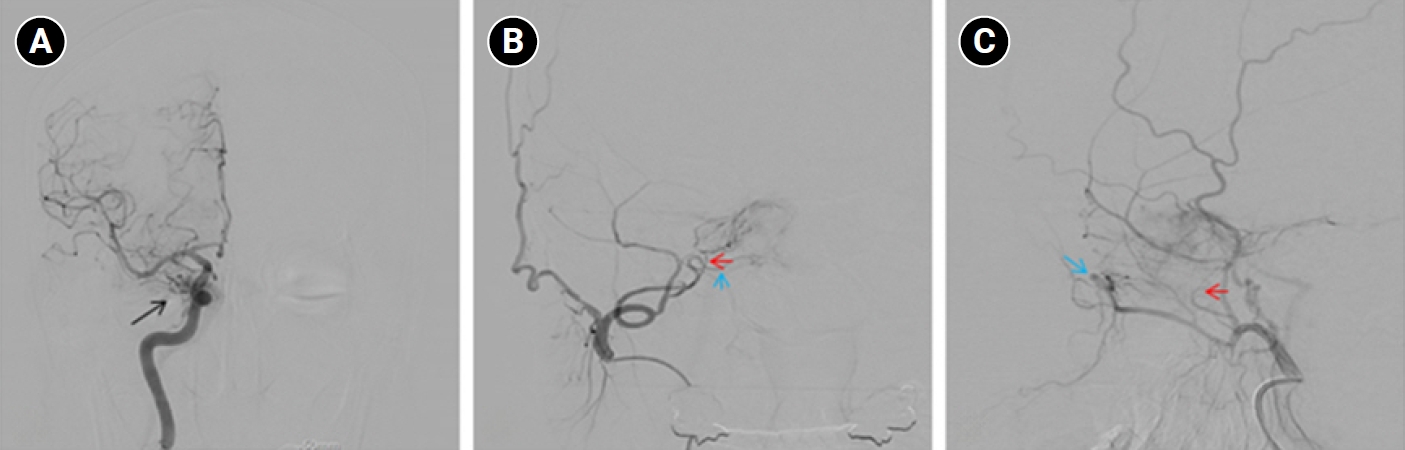

Baseline hematology and chemistry—including complete blood count, electrolytes, renal/hepatic indices—and coagulation tests (prothrombin time/international normalized ratio, activated partial thromboplastin time) were within reference limits. Erythrocyte sedimentation rate and C-reactive protein were normal. A focused screen for secondary trigeminal neuropathy (thyroid-stimulating hormone, vitamin B12, HbA1c) was negative. There were no clinical signs of infection. Brain magnetic resonance imaging (MRI) demonstrated high flow related signal in the right cavernous sinus and asymmetric dilation of the superior ophthalmic veins (right>left), raising suspicion for a CCF (Figure 1). Definitive diagnosis was established on digital subtraction angiography (DSA), which identified a right CCF. DSA demonstrated an indirect CCF supplied by the right meningohypophyseal trunk of the ICA and by right ECA branches, including the internal maxillary artery and the cavernous branch of the middle meningeal artery, consistent with Barrow type D (Figure 2).6 Barrow type D denotes an indirect, low-flow fistula with dual ICA/ECA dural supply; unlike direct type, indirect types present more insidiously, and symptom patterns are largely determined by venous drainage, with posterior drainage often manifesting as CN VI palsy and headache (Table 1).1,3,6,7 The fistula was treated with transvenous Onyx embolization. On post-procedure day 1, non-contrast time-of-flight magnetic resonance angiography (TOF-MRA) demonstrated a marked reduction of flow related hyperintensity within the right cavernous sinus, and the right superior ophthalmic vein caliber decreased from 6.63 to 4.61 mm (Figure 3A, B). Follow-up DSA (at 3 weeks) likewise showed substantial attenuation of fistulous opacification (Figure 3C), supporting a significant interval decrease in arteriovenous shunting. At 1–2 weeks, the patient reported an ~80%–90% reduction in dental/lower-facial pain and bifrontal headache from NRS 7–8 to 1–2. By 1 month, red-glass testing demonstrated resolution of primary-position diplopia. Formal prism measurements were unavailable; bedside ocular-motor grading was recorded using a standard duction underaction scale (–4 to 0). Right abduction improved from –1 to 0, and primary-position diplopia was absent at distance and near, consistent with recovery from abducens palsy.

Figure 1.Brain magnetic resonance imaging (MRI) findings. (A, B) Non-contrast time-of-flight magnetic resonance angiography shows a high flow-related signal (red arrows) within the right cavernous sinus. (C) Contrast-enhanced T1-weighted MRI demonstrates asymmetric dilation of the superior ophthalmic veins (blue arrow), more prominent on the right.